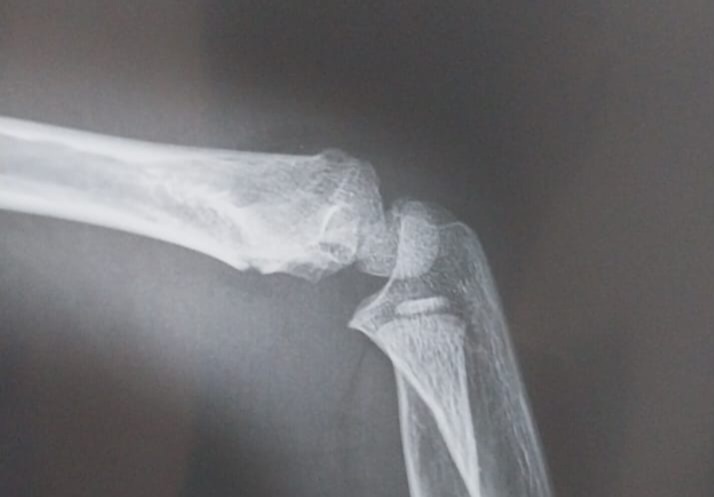

На этом снимке вообще почти не видно, что есть перелом, но трещина была заметна на снеимке в другой плоскости

Муж просит администратора послать врачу снимок, чтобы зря не ждать. Врач присылает ответ - перелом есть, но именно в этой клинике у него гипса нет. Гипс есть в другой клинике, в которой он принимает с 7.30 вечера. Район тот же, разные локации. С 5.30 до 7.30 эта клиника, с 7.30 - вторая.